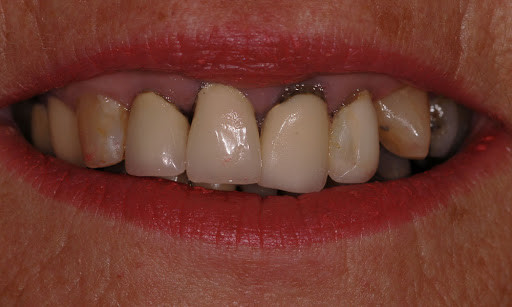

What Causes The Dark Line On My Gums?

You have seen smiles that you know have dental crowns in the front. You look at them and say to yourself that something is not natural. Many times, it is the dark rim of gum tissue that gives it away. The dark rim of gum tissue does not occur around natural teeth, only around teeth that have been covered with dental crowns.

The dark line is associated with an old porcelain dental crown. This style of dental crown is referred to as a porcelain fused-to-metal dental crown because it uses tooth-colored porcelain on the outside and it uses metal under the porcelain for strength. The dark line originates from the edge of the dental crowns where the porcelain and the metal meet at a knife-edge at the gum line. At the knife-edge, a very thin amount of the metal always shows. One of the illusionary techniques cosmetic dentists have used was to hide the thin dark line under the gum line. Over time, the gum tissue would recede and expose the dark line. In some patients the dark line would show through the gum and make it appear dark as well.

How Do You Get Rid of It?

The only way to eliminate the esthetic problem is to replace the dental crowns. When replacing just one single dental crown in the front, you should expect that it might take more than one try-in of the new dental crown before it is permanently cemented into place. Because your central incisors are the most prominent teeth in the mouth, matching them is the most difficult esthetic challenge. Only the best dental technicians are able to mimic one central incisor tooth next to another.

What Are Some of the Replacement Dental Crowns Like?

Some of the clever ways dentists and dental technicians have been able to mimic natural teeth is through the new advancements in dental materials. New all-tooth-colored ceramic dental crowns are the latest technological advancement cosmetic dentists have to recreate natural teeth. In comparison to porcelain fused-to-metal dental crowns, all-ceramic dental crowns do not contain any metal, thus no dark line can appear.

Some advantages and disadvantages of all-ceramic dental crowns are as follows:

Advantages of All-Ceramic Dental Crowns

High esthetics

Excellent fit

If gum recession occurs, there is no dark line

Disadvantages of All-Ceramic Dental Crowns

Not as strong as porcelain-fused-to-metal dental crowns

Cannot be used in all areas of the mouth.